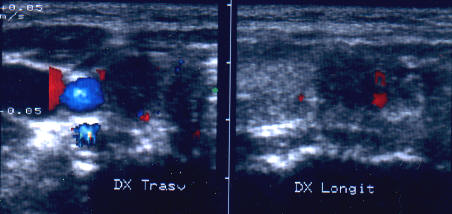

ecocolordoppler si powerdoppler- acelasi nodul

Vascularizatie interna, mai evidenta in powerdoppler.

Femeie 25 ani. Nodul unic in lobul stang, contur net, hipoecogen, respecta parenchimul din jur, neomogen, de 18x23x36 mm (7,5 cc).

Citoaspiratia cu ac subtire: nodul adenomatos.

Examen histologic postoperator: adenom trabecular fetal.

Acelasi caz. La doppler color - vascularizatie interna, mai evidenta in powerdoppler.